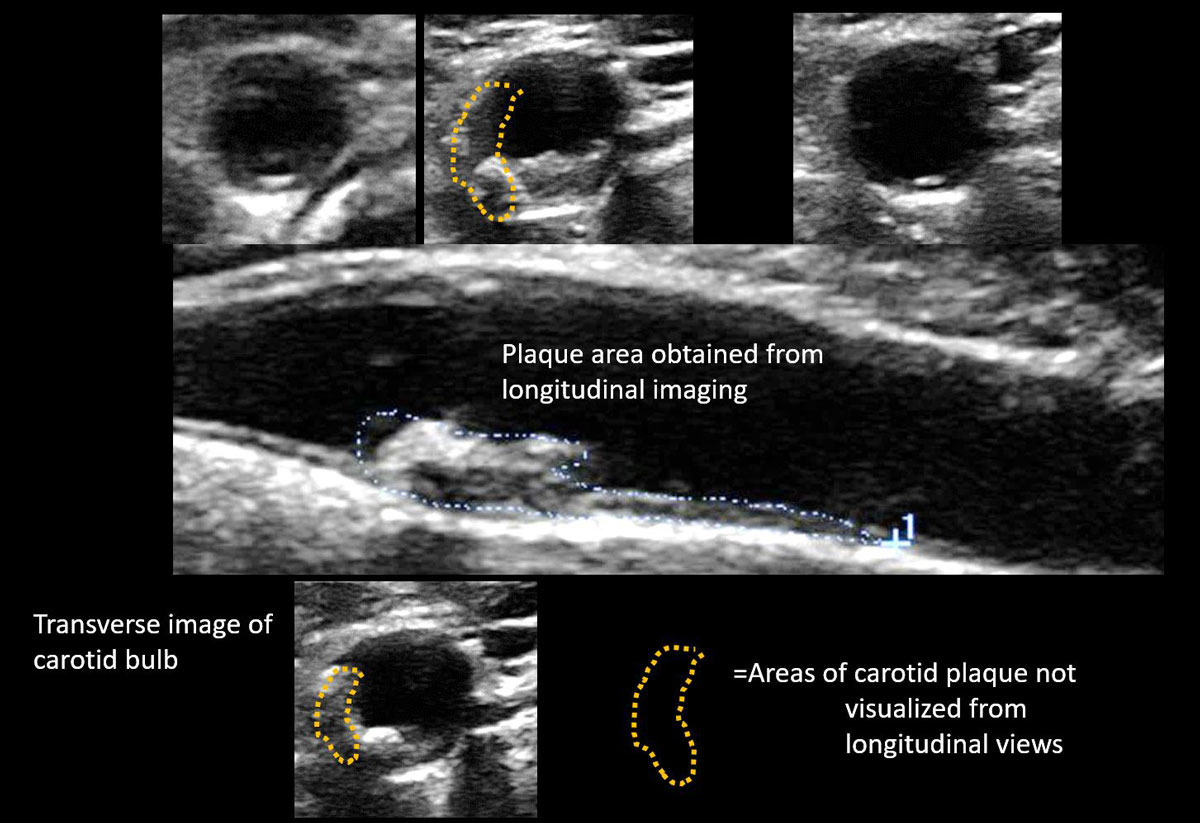

경동맥 초음파(Carotid Ultrasound)는 목 양쪽에 위치한 경동맥(carotid artery)의 혈류 상태를 확인하는 비침습적 영상 진단법입니다. 경동맥은 뇌로 혈액을 공급하는 주요 동맥으로, 이 부위에 죽상경화(동맥경화)가 발생하면 뇌졸중(중풍)이나 일과성 허혈 발작(TIA) 등 치명적인 뇌혈관 질환으로 이어질 수 있습니다.

이 검사는 초음파를 통해 경동맥 내벽의 두께, 혈류 속도, 혈전이나 협착(좁아진 부분) 여부 등을 정밀하게 경동맥 초음파 검사로 알 수 있는 병들을 관찰하여, 뇌졸중 위험성을 사전에 파악할 수 있는 중요한 예방 의료 행위입니다.

- 혈관벽에 지방 찌꺼기(죽종, plaque)가 축적되어 탄력을 잃고 혈류를 방해하는 상태입니다.

- 내중막 두께(IMT) 측정으로 혈관 노화 정도를 정량화할 수 있습니다.